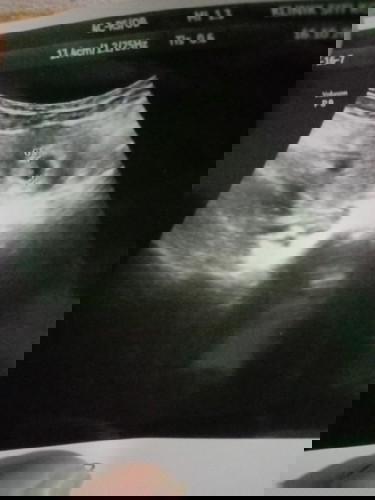

Normal ka preggy 6 minggu nampak kantung sahaja?.. risau jugak sebenarnya..4 kali dah scan

Normal sbb kecik lg, nk nampak isi tu susah. Tunggu dah 8 minggu ke atas, selalunya masa tu dh boleh nampak dah janin dan dgr heartbeat.